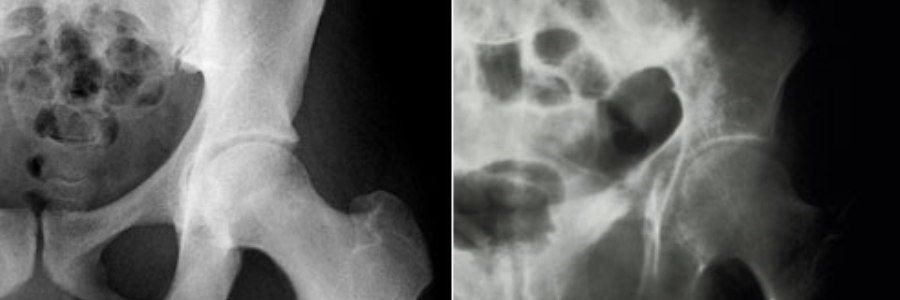

پوکی استخوان یک اختلال اسکلتی است که ویژگی بارز آن کاهش استحکام استخوان بوده و فرد را در معرض خطر شکستگی قرار می‌دهد. این بیماری در دوران یائسگی زنان بسیار شایع است زیرا در این دوران استروژن بسیار در بدن زنان کم می‌شود. بدلیل عوارض جبران ناپذیر این بیماری پیشگیری از آن دارای اهمیت ویژه می باشد.